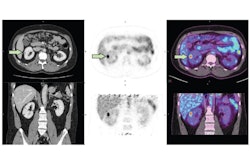

An emerging PET radiotracer fills an unmet need to identify small lesions in the kidney, which could allow earlier diagnosis of clear-cell renal cell carcinoma, a multinational research team has reported. Check out our article.